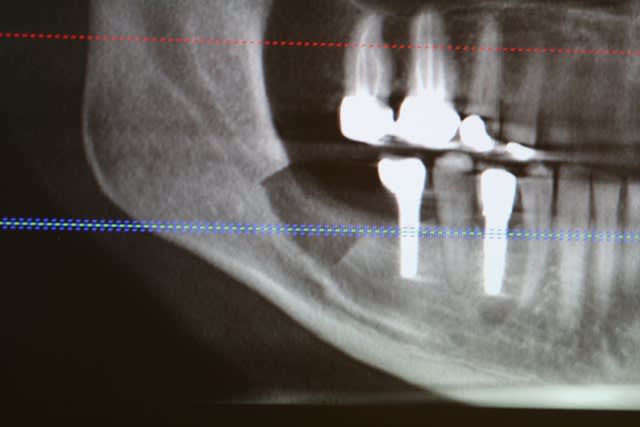

image 10: radio post op

image 11: tomo à 4 mois

image 12 et 13: réouverture, forage et pose des implants ( les implants ont été posés par le DR A. L dans le 31)